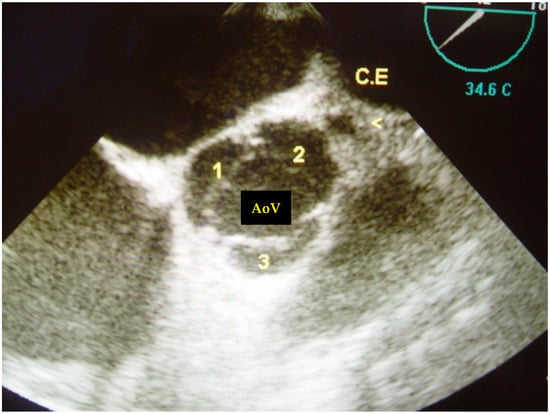

Case Description